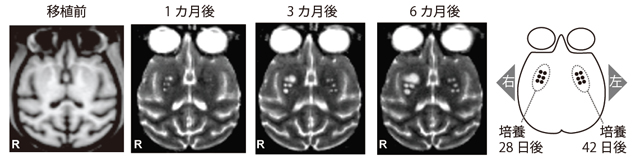

まず、MRIを用いた解析の結果、移植後6ヶ月まで移植細胞は生き残っていることを確認できました(図3)。特に42 日間培養した細胞の方が、移植片が小さいことが明らかになりました。また、PETを用いた解析によって、42日間培養した細胞の方がよりドーパミン神経細胞として機能していることが示唆されました(図4)。さらに、脳切片の免疫組織学的解析で、42日間培養した細胞の方が、より多くのドーパミン神経細胞に分化していることが確認できました(図5)。 また、ビデオ撮影やスコア判定を利用した行動の解析も行いました。

- 図3 MRI画像による移植片サイズの解析

左右に6箇所ずつ移植し(中央前方よりの白い点)、6ヶ月後も細胞が生存していることが確認できた。28日間培養した細胞(右側:R)と比べると、42日間培養した細胞の方が移植片が小さい。